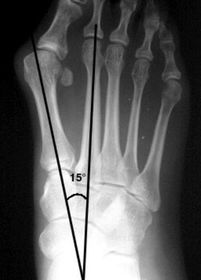

| What angle is this? Is this normal or abnormal? | 1st intermetatarsal angle Abnormal. Greater than 9 degrees is abnormal. Usually due to metatarsus primus varus |